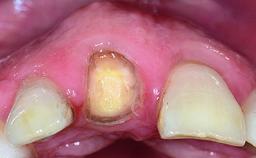

A 32-year-old female Caucasian patient with a compromised maxillary right central incisor was referred to us by a general dentist. Her chief complaints were discomfort and mobility of tooth 11 with unsatisfactory esthetics due to discoloration. The patient reported a previous trauma, some years earlier, as the origin of pathology on the afflicted tooth. Anamnesis was negative for any other dental or periodontal pathology in the remaining dentition. The patient did not take any medication and reported to be a light smoker (5–10 cigs/day). She had high esthetic expectations of her treatment. The extraoral examination revealed a high smile line with full exposure of her maxillary teeth and surrounding soft tissue in the area between the second premolars.

Bone Volume Deficient horizontally, requiring prior grafting

Soft Tissue Contour and Volume Slightly compromised